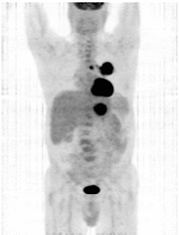

Fig. 3. Structura 18F-FDG, in comparatie cu Fig. 4. Imagine PET cu F FDG:

D-glucoza si 2-deoxi-D-glucoza neoplasm pulmonar primar (lob superior stang) cu

metastaze (paratraheal si in lobul hepatic stang)